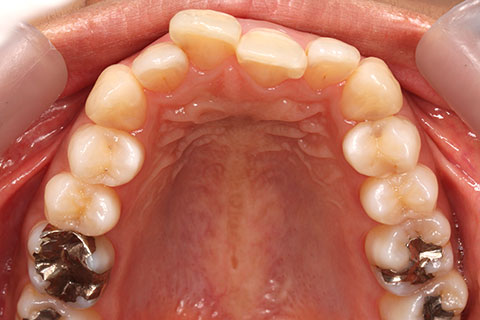

治療前

治療中

治療後

- 年齢・性別

- 23歳女性

- 治療期間

- 1年6ヶ月

- 抜歯

- 上顎4番

- 治療費

- 110万円(税込み)

- 備考

- ハーフリンガル矯正

- 治療内容

- 上下前歯部凸凹の改善

- 施術の副作用(リスク)

- 裏側矯正の特性上、表側矯正と比較すると治療期間が長くかかる場合が多い。